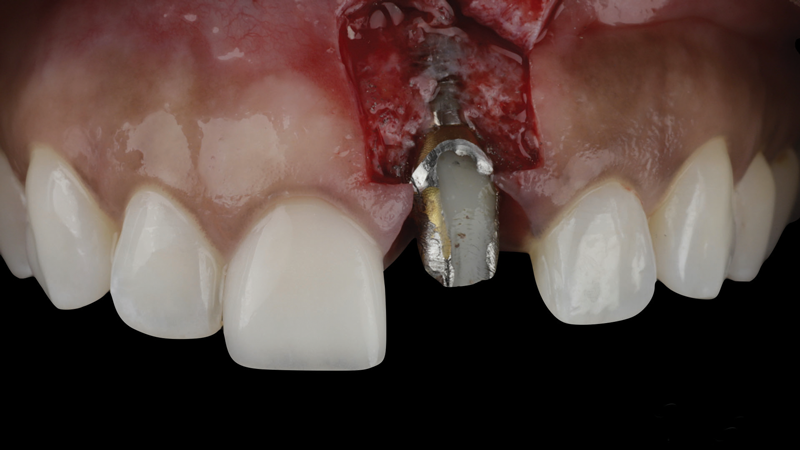

The patient in this case had undergone implant therapy at the site of tooth No. 9 and was restored with a cement-retained restoration more than 5 years prior. At presentation, the site demonstrated a peri-implant soft-tissue dehiscence that extended approximately 3-mm apical to the gingival margin of tooth No. 8. Thin and erythematous marginal tissue was evident at the zenith (Figure 2). The crown was removed, and a partial thickness flap was reflected using a papilla-sparing incision design. This revealed that the implant was positioned too far facially and that its body was visible through a very thin layer of bone (Figure 3 and Figure 4). The first objective of treatment was to minimize the facial extent of the emerging abutment and crown. To accomplish this, the facially positioned abutment and implant crown margin were both recontoured. The second treatment objective was to provide additional supracrestal soft tissue that would more adequately maintain the peri-implant margin. The tuberosity was selected as a donor site due to its dense, high-quality connective tissue, low propensity for shrinkage, and association with minimal patient discomfort. Once the graft was secured (Figure 5 through Figure 7), the flap was coronally positioned (Figure 8). After a healing period of 2 weeks, the margin of tooth No. 9 exhibited an ideal position in relation to its contralateral counterpart and demonstrated increased soft tissue thickness (Figure 9). Three months postoperatively, further healing had improved the esthetics and the position of the margin had been maintained (Figure 10).

(3.) The crown was removed, and a partial thickness flap was reflected using a papilla-sparing incision design, which revealed that the implant was positioned too far facially and that its body was visible through a very thin layer of bone.

Figure 3

(4.) The crown was removed, and a partial thickness flap was reflected using a papilla-sparing incision design, which revealed that the implant was positioned too far facially and that its body was visible through a very thin layer of bone.

Figure 4